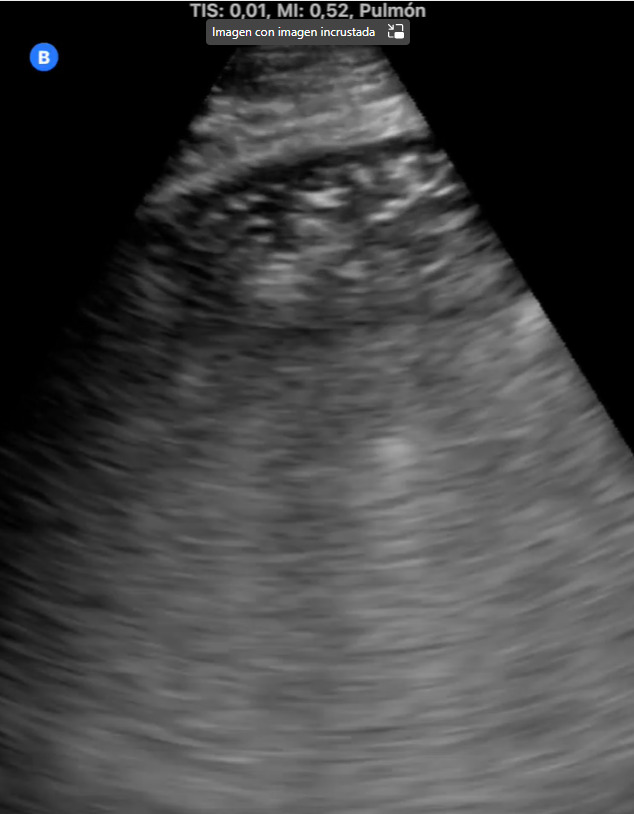

La ecografía pulmonar nos permite aumentar la capacidad diagnóstica y resolutiva, con gran rapidez y gran número de situaciones clínicas, disminuyendo el nivel de incertidumbre. Nos ayuda a tomar decisiones y ofrecer un mejor cuidado a los pacientes. Permite evaluar la extensión y gravedad de la enfermedad, así como monitorizar la progresión y evaluar las complicaciones.

Además, ayudándonos de la ecografía pulmonar, hemos podido diagnosticar diferentes patologías pulmonares intersticiales como neumonitis intersticial por metotrexate, neumopatía intersticial tipo NINE y síndrome alveolo intersticial.

La ecografía es una herramienta valiosa en la evaluación y manejo de patologías pulmonares intersticiales, proporcionando información clave que puede influir en el tratamiento y pronóstico del paciente.